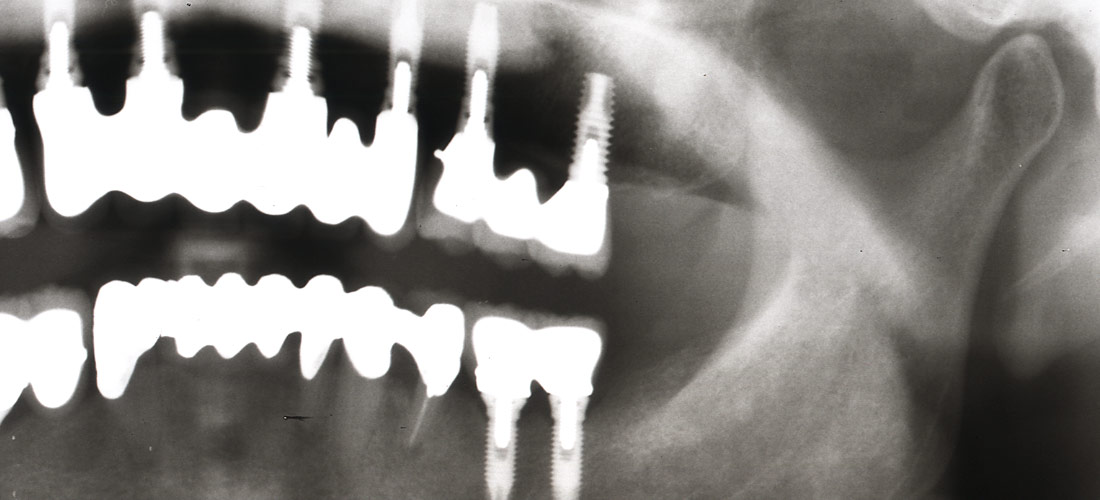

術前

歯根分岐部に影。

同CT像。

大きな骨の欠損欠損が認められます。

術後2ヶ月目の写真。

分かりにくいですが、歯根分岐部の骨が再生しつつあることが確認できます。